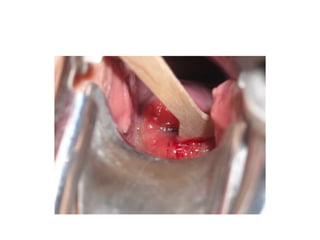

Colposcopy

• Colposcopy is done

• when abnormal findings on cytologic examination

• who do not have a gross cervical lesion must be evaluated

with colposcopy and directed biopsies.

• To study extend of abnormal lesion

• Conservative surgery under colposcopic guidence

• Following application of a 3% acetic-acid solution, the cervix is

examined under 10- to 15-fold magnification with a bright,

filtered light that enhances the acetowhitening and vascular

patterns characteristic of dysplasia or carcinoma.

• Abnormal area are acetowhite area,mosaics,punctuation and

abnormal vessels.